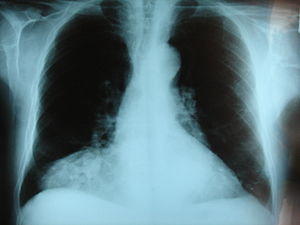

Hernia de Morgani.JPG

Morgagni hernia seen on a chest radiograph.